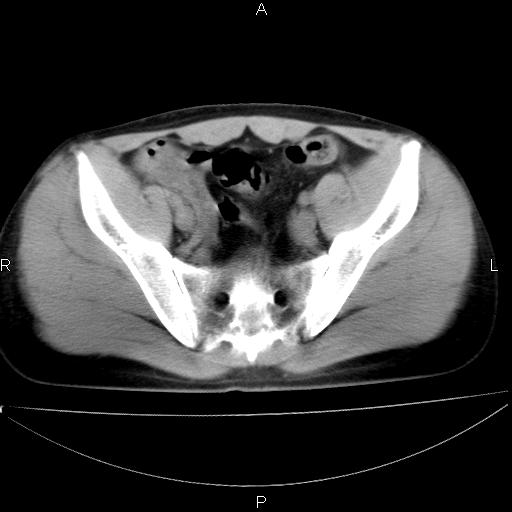

男 25岁 自述 尿频尿急,排尿困难20多天.无腰痛, b超说左肾盂轻度积水,左输尿管上端扩张.未见结石影. ct我看双侧肾盂轻度积水,双输尿管上端都扩张,大家看看能看见结石吗?

双输尿管扩张下端未见高密度结石和输尿管晕轮征,不好说是结石.增强后如何?

双肾轻度积水,未见明确结石,薄层对结石检出率较高。

双侧输尿管上端扩张,未见明确结石,可进一步ivp检查。

双肾盂及双输尿上段轻度积水,双输尿管未见明显结石影。